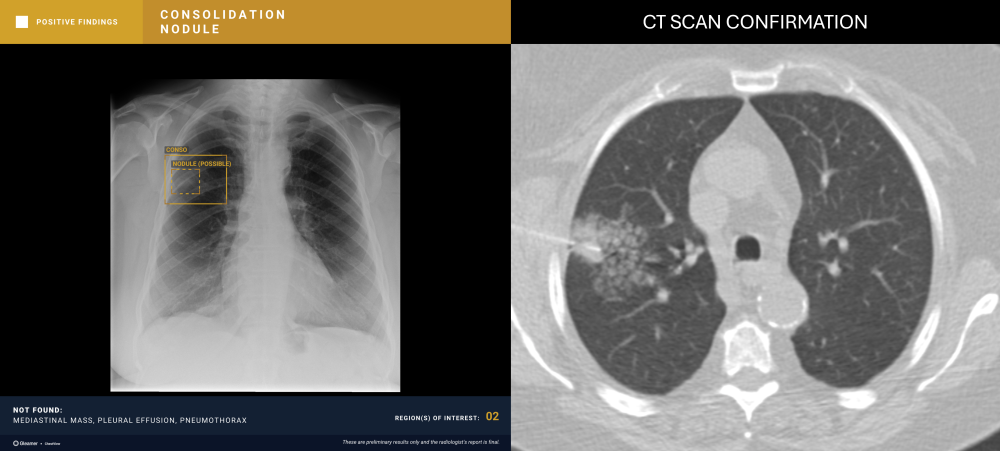

A 40-year-old female with a history of colon cancer presents for a control radiograph following biopsy of a right lower-lobe pulmonary nodule.

ChestView detected a pneumothorax post-biopsy.